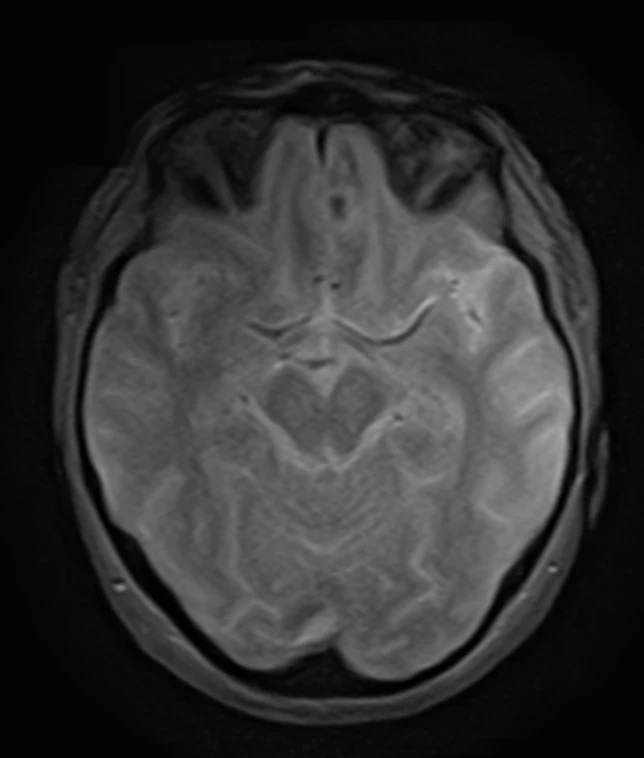

Наконец-то я увидел это воочию! Киста полости Верги, промежуточного паруса, осложнённая гидроцефалией. Из анамнеза: Низкое артериальнео давление, нарушение речи, затуманенное сознание, головная боль, головокружение, в 1989 году перенёс менингит.

А Вы видали такое? Я впервые вижу, раньше только читал в литературе.